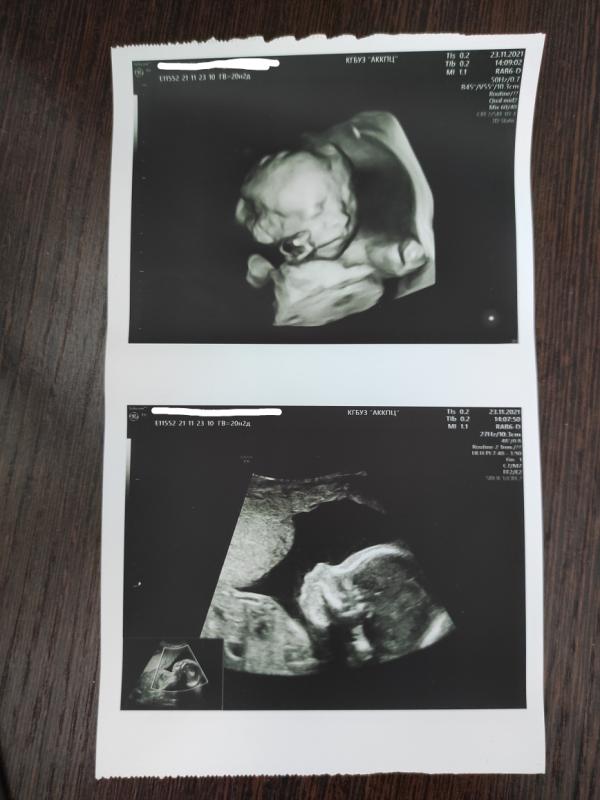

✅20 недель 3 дня

✅2 скрининг пройден

У нас будет еще один сынок 👶

Развивается малыш хорошо. Правда, по всем размерам на 22,3 недели 😀 420 гр счастья💪 Думаю, крупняш поди будет? Старший родился 3700, 54 см. У нас и есть в кого - все высокие и крупные в родне))